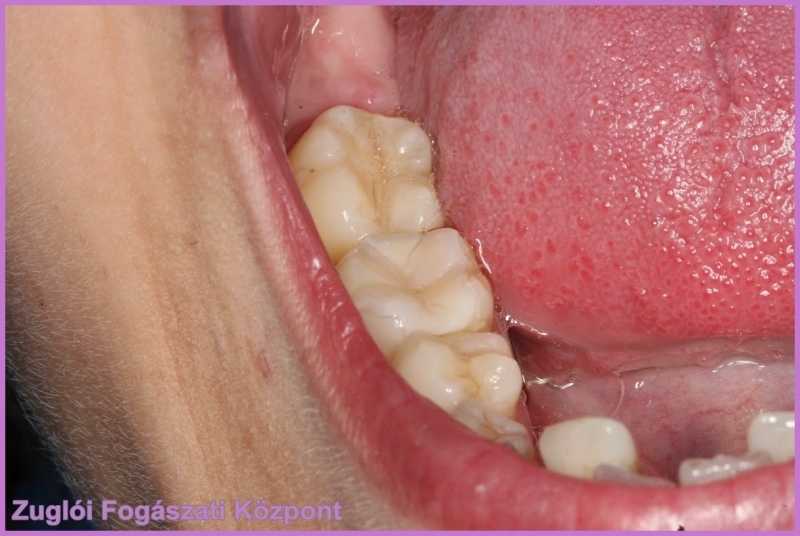

Ezután a hölgypáciens visszakerült Dr. Holló Ádámhoz, aki a hiányzó fogdarab kiterjedése miatt esztétikus kompozit (Gradia) inlay-t javasolt. A törött fogról lenyomatot vett, ez alapján a fogtechnikai laborban elkészült az inlay (betét), amelynek színét a páciens fogaihoz igazították. Íme, a szépen helyreállított fog!

gradia inlay készült a törött foghoz.